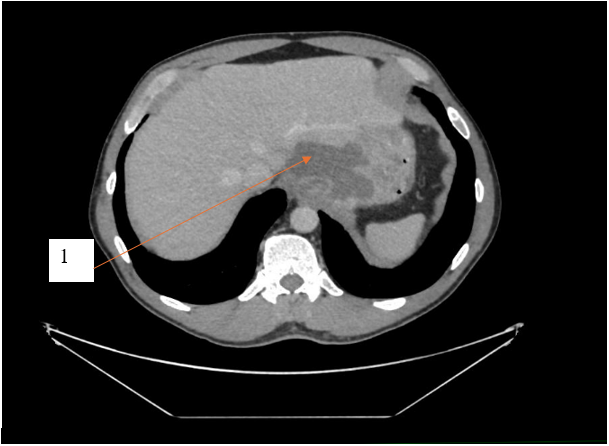

По данным компьютерной томографии органов брюшной полости с внутривенным контрастированием выявлена структура жидкостной плотности в области кардиального отдела желудка без убедительной связи с просветом желудка. Единичные увеличенные параэзофагельные, паракавальные, парааортальные лимфоузлы. Другой патологии не выявлено. Результаты компьютерной томографии с внутривенным контрастированием представлены на рисунках 1 и 2.

Рис. 1. Компьютерная томограмма с внутривенным контрастным усилением, пациент К., 54 года, фронтальный срез, отсроченная фаза. 1 – структура жидкостной плотности в области кардиального отдела желудка

Fig. 1. Computed tomogram with intravenous contrast enhancement, patient K., 54 years old, frontal section, delayed phase. 1 – liquid density structure in the cardiac region of the stomach